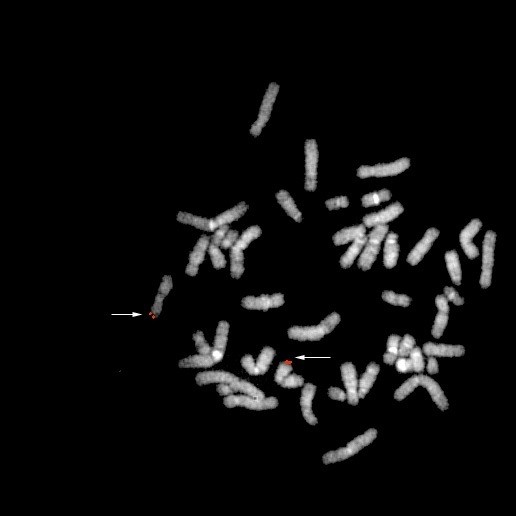

bA11A9